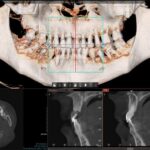

Virtobot atualizou o anterior. Atualmente com sua nova versão atualizada, o Virtobot melhorou a precisão da biópsia e está focado em agilizar o fluxo de trabalho e aumentar o nível de automação. Recentemente, técnicas mais avançadas de digitalização 3D foram introduzidas, permitindo imagens multiespectrais de corpo inteiro. A imagem utilizou fotogrametria multiespectral de 365 nm a 960 nm usando uma câmera digital com melhorias nas fontes de luz ultravioleta e infravermelha próxima e filtros de lente para revelar possíveis traços dentro do corpo. Fluidos corporais, hematomas, etc. Para detectar cadáveres através da arcada dentária (Crânio Facial), é utilizada outra ferramenta de radiologia forense a virtual autópsia dentária, a mesma foi projetada para melhor atender às necessidades dos setores judicial e criminal.

O Instituto de Identificação Humana da Universidade de Turim e o Gabinete de Assuntos Médicos e Jurídicos lançaram um projeto de pesquisa em 2020 com base na hipótese de que o processo de identificação de corpos não identificados deve sempre seguir os melhores protocolos para esclarecer a identificação de corpos, disse,( Nuzzolese, E. 2021). deve sempre incluir um exame odontológico completo para complementar e documentar a autópsia mesmo quando um dentista forense não estiver no local. Além disso, ferramentas virtuais em medicina e odontologia também podem ser utilizadas em medicina forense, especialmente para identificação pessoal,após a pandemia de COVID-19 e o risco potencial de infecção obrigou as instituições forenses a realizar autópsias virtuais sem comprometer as informações técnicas fornecidas pelo dentista forense. Atualmente, poucos departamentos ao redor do mundo reconhecem a viabilidade da autópsia tele dental, mas algumas instituições oferecem consultas remotas em odontologia legal para identificação pessoal ou oferecem este serviço por motivos humanitários. O projeto reúne temas de pesquisa como patologia, odontologia, antropologia e arqueologia, sob a égide dos direitos humanos dos mortos e da odontologia forense humanitária. O termo VIRDENTOPSY é uma combinação dos termos “virtual” e “anatomia dentária”. Esta é uma marca registrada de um site dedicado a fornecer avaliação odontológica forense remota de dados dentários post-mortem de restos mortais não identificados. O uso de radiografias em odontologia legal visa facilitar a identificação de corpos por meio do exame de detalhes anatômicos que podem ser utilizados como parâmetros. Isso inclui o formato dos dentes e raízes, dentes ausentes e existentes, raízes remanescentes, dentes supranumerários, fricção e desgaste e fraturas radiculares, grau de

reabsorção óssea devido à periodontite, lesões ósseas, diastema, formato e linha da cavidade, cáries, terapia endodôntica, pinos intrarradiculares e próteses dentárias. (Eastman, R., Raibley, et al 1982).

O processo de identificação de restos mortais não identificados deve respeitar os mais elevados padrões forenses e deve incluir sempre a recolha de todos os dados de identificação post-mortem. A tomografia cone beam(TCFC) é um método radiológico caracterizado por alta resolução espacial e baixa dose de radiação, adequados para diagnóstico prognóstico quando são identificados resíduos desconhecidos. Esses métodos permitem obter imagens precisas e detalhadas das estrutura dentárias e craniofaciais, essenciais para a identificação post mortem de indivíduos.Este processo requer a comparação de pessoas desaparecidas correspondentes com dados ante-mortem documentadas e a reconciliaçãofinal de todos protocolos(Da Luz Silva, W., Dias, R. S., Vergara, C. S., & De Sá, L.

- 2023). Neste contexto, uma autópsia dentária completa e uma avaliação adicional de todos os achados dentários por um dentista legista são essenciais para obter um perfil biológico geral e um exame geral.Simples exames dentários e recolha de dados dentários sem avaliação por especialistas em odontologia forense e identificação de vítimas não podem dar um contributo tangível para uma identificação pessoal atempada e eficaz. É necessária uma recolha e análise mais abrangentes de dados post-mortem quando se consideram os fenómenos migratórios Em Itália, o Projecto Migrantes Desaparecidos estima que houve 124 mortes e desaparecimentos de migrantes desde 2014, e mais de 60 dessas vítimas não foram identificadas As avaliações odontológicas forenses, por outro lado, limitam-se a exames odontológicos de não vítimas.Dentistas forenses experientes parecem estar rotineiramente envolvidos as aplicações de anatomia virtual em odontologia forense incluem a coleta de dados dentários e a comparação de ortopantomografias post-mortem O processo de virdentopsia não apenas integra a dissecção virtual na prática da odontologia forense, mas também depende de vídeo 2D e 3D, fotografia e fotogrametria, bem como imagens de raios X e tomografia computadorizada.documentação.

A dissecção virtual permite que os dentistas examinem mandíbulas e dentes sem realizar uma dissecação dentária tradicional ao envolver dentistas remotos de vários países sem a necessidade de estarem fisicamente presentes, a Virdentopsia expande os horizontes desta abordagem virtual e tem o potencial de se tornar o padrão para todos os restos mortais não identificados recuperados(Nuzzolese, E. 2021).Uma radiografia típica é baseada na comparação de radiografias ante-mortem e post-mortem mantidas em um consultório ou centro de pesquisa odontológica. Esses raios X fornecem muitas informações sobre a pessoa.